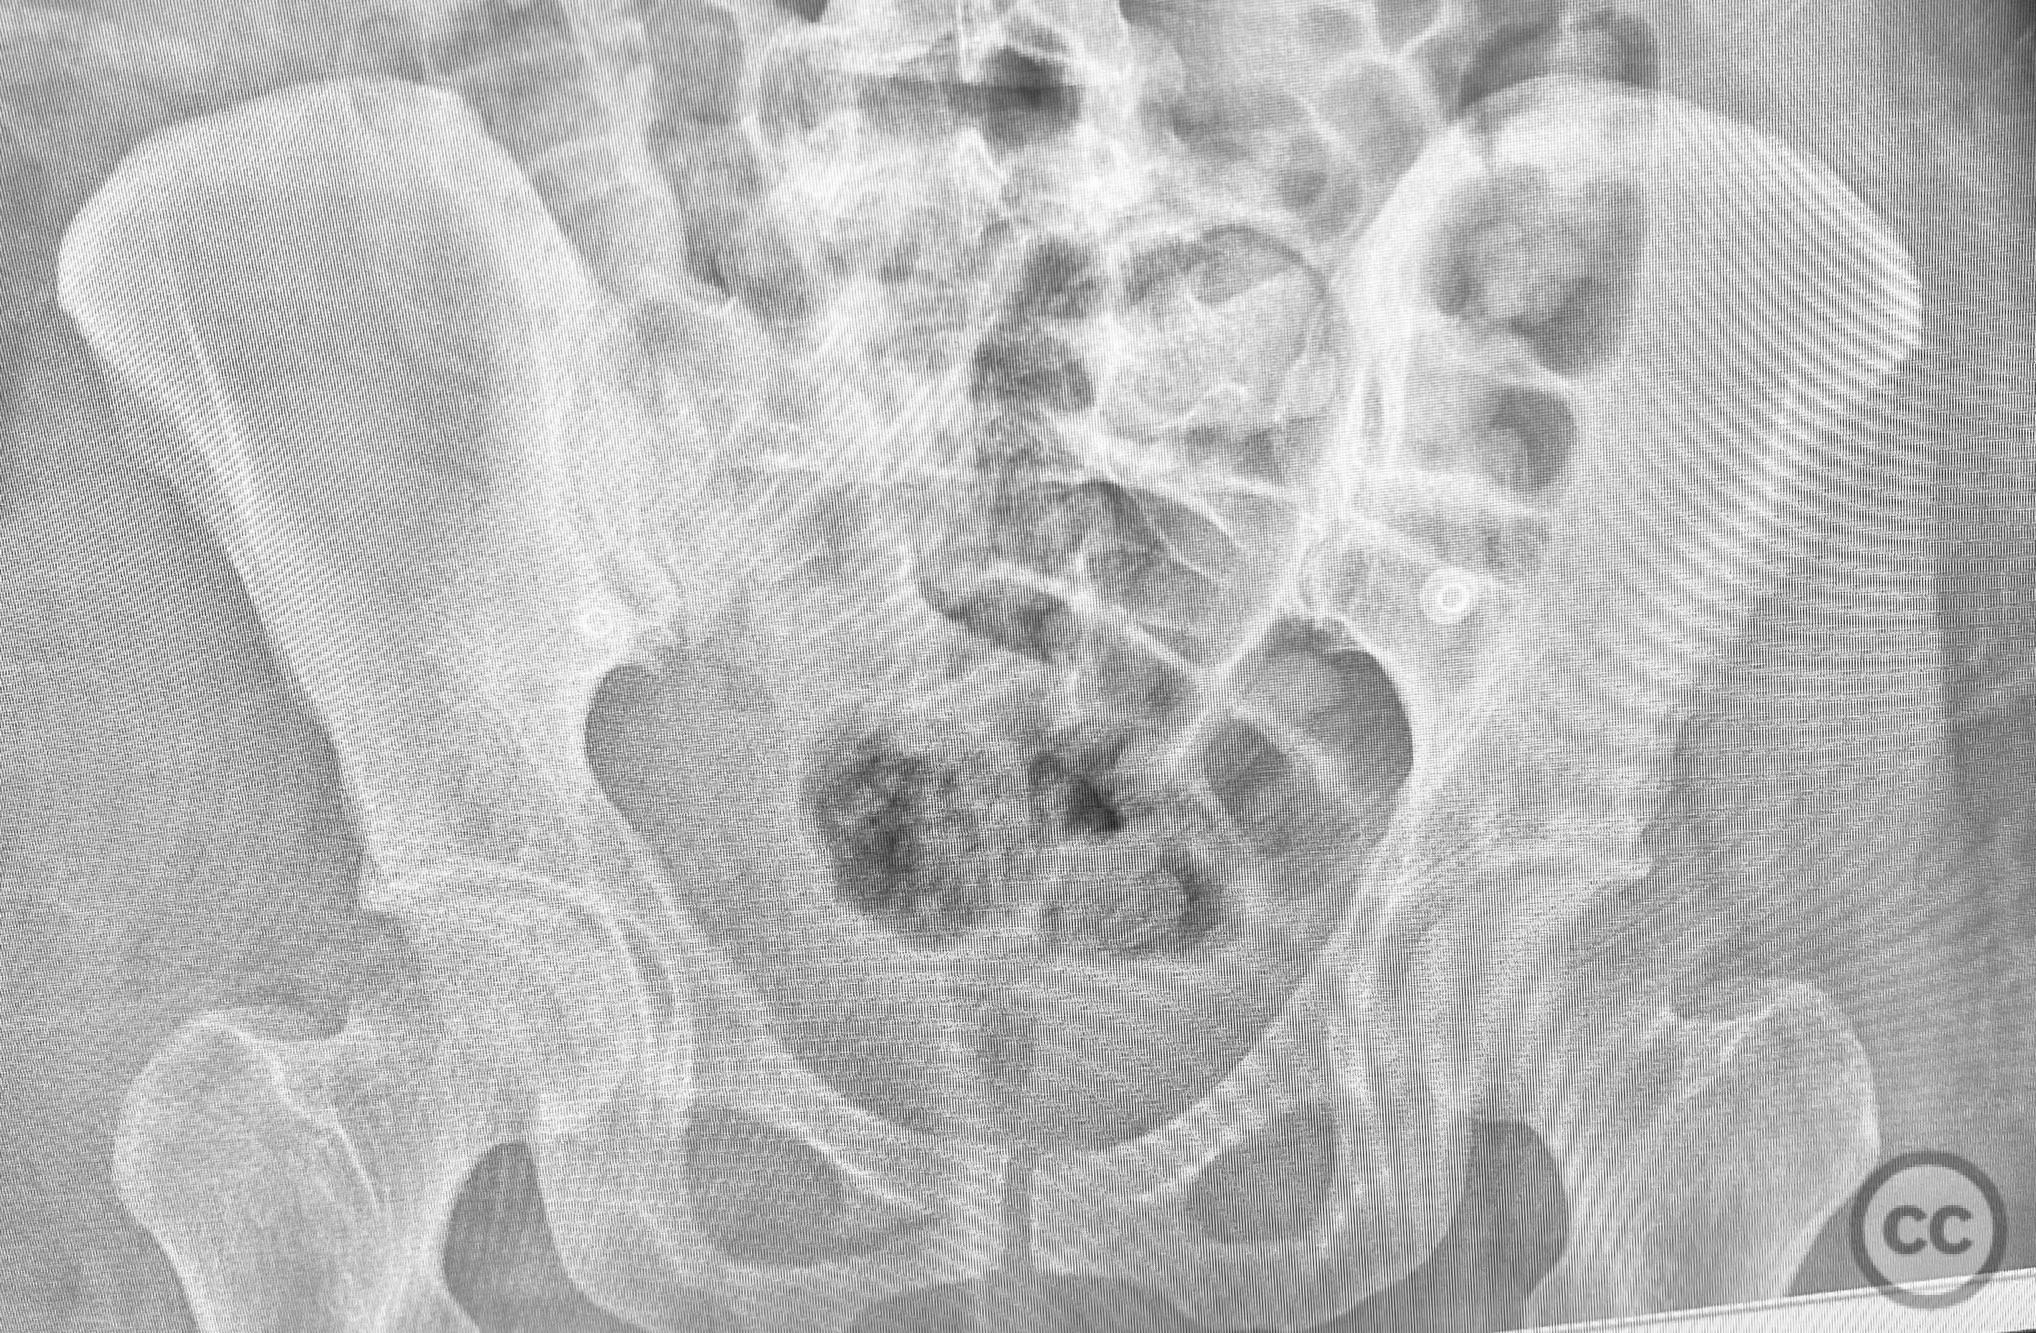

Clinical and radiological findings:  A middle-aged patient involved in a motor vehicle collision presented initially with a closed ankle fracture-dislocation and minimal pelvic complaints. Following closed reduction and splinting of the ankle, the patient developed severe pelvic pain (9/10) with any attempted movement. Neurological and vascular examination was not specified. Computed tomography demonstrated minimally displaced fractures of the posterior ilium, sacral ala, and bilateral pubic rami. AP CT surface renderings revealed subtle but clinically significant displacement and deformity of the pelvic ring, which was difficult to appreciate on standard axial images.

Intraoperative assessment confirmed instability at the posterior pelvic ring with manual stress testing under fluoroscopy. Reduction was achieved with gentle manipulation and maintained during percutaneous screw insertion. The use of intraoperative inlet and outlet views was critical for accurate screw placement and confirmation of reduction. The minimally invasive technique minimized additional soft tissue trauma in this polytrauma patient.